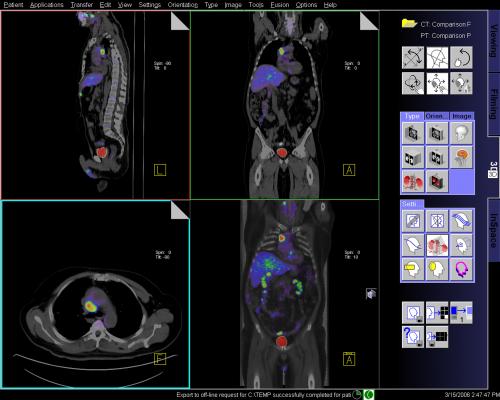

Doctors funded by Cancer Research UK and international partners in Europe and Australasia used positron emission tomography (PET) to scan more than 1,200 patients with advanced Hodgkin lymphoma after they had been given two cycles of standard chemotherapy.